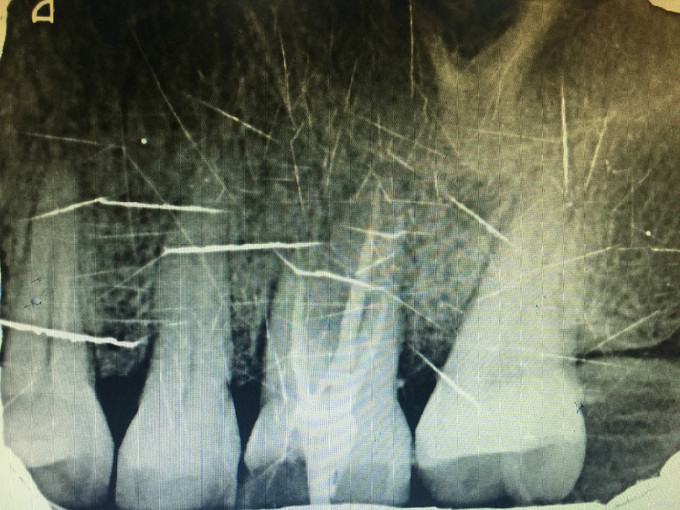

临床检查:26近中龋坏可探及穿髓点,无窦道,探疼(+),冷(++),叩(-),松动度(-),牙周红肿,牙石1度 辅助检查:X线示26龋坏累积髓腔。

诊断:26牙髓炎 治疗:经患者知情同意后,26局麻去腐降牙合,开髓拔髓寻找根管口,建立直线通路,扩通根管,确定工作长度。S3/EDTA凝胶镍钛器械,次氯酸钠冲洗根管,预备至35/04,氢氧化钙诊间封药,一周后复诊,试主尖X线示恰充,试干根管,导AH-PLUS糊剂,VDW热压胶垂直加压根充,术后见根管恰充,暂封调合抛光。树脂充填。